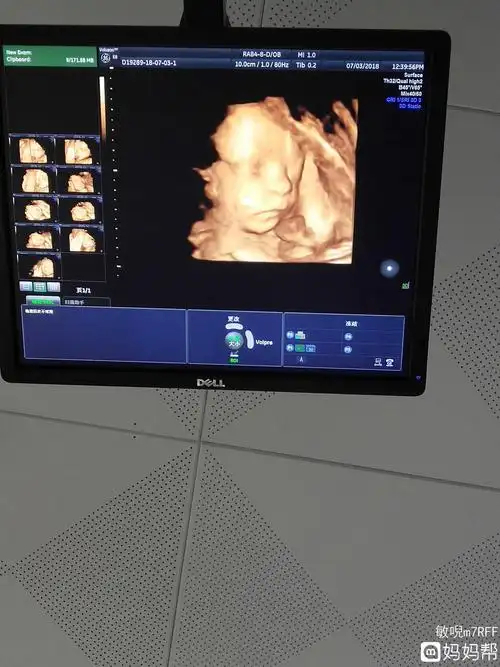

生机勃勃!六个月四维彩超男孩图"一往无前"-第2张图片-途威网